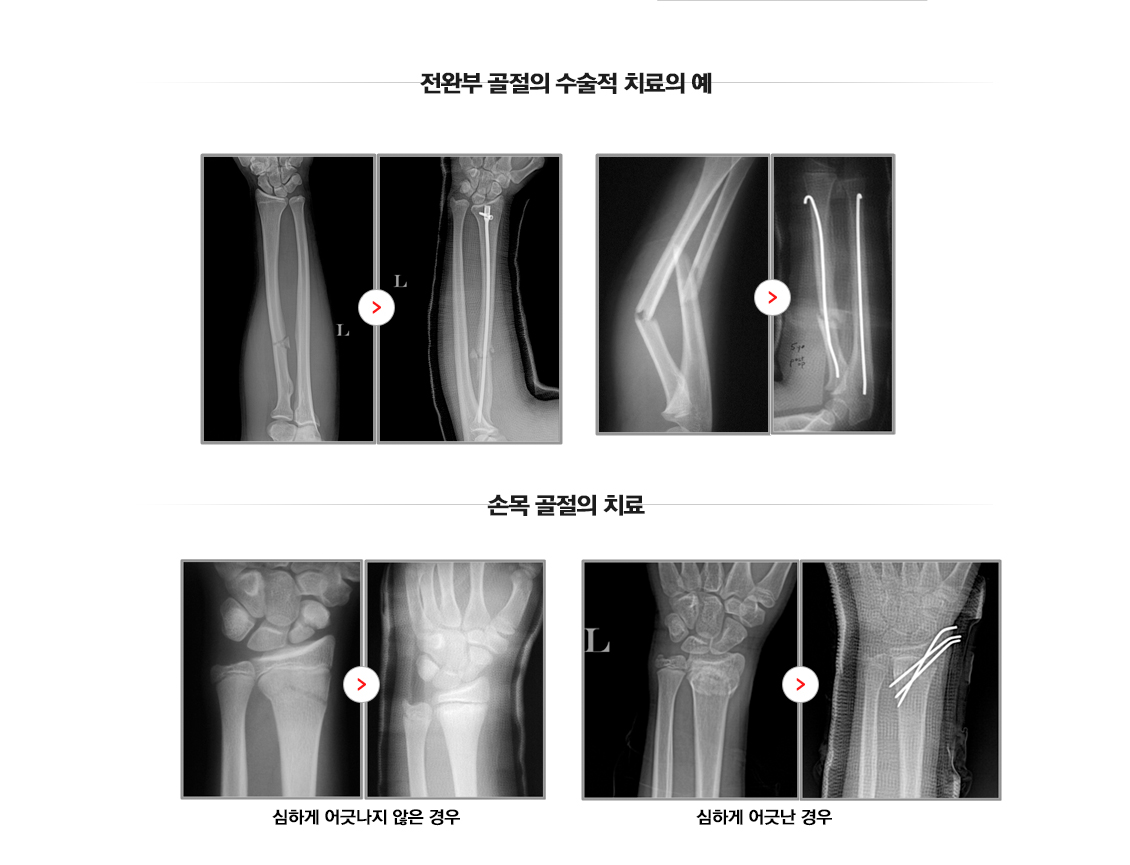

관절주위골절(손목)

손목 골절수술

Wrist Fracture